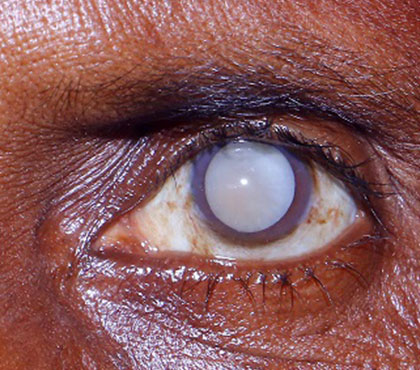

अंधापन

रक्त वाहिकाओं को नुकसान जिसके कारण दृष्टि की हानि या दृष्टि का पूर्ण नुकसान होता है।